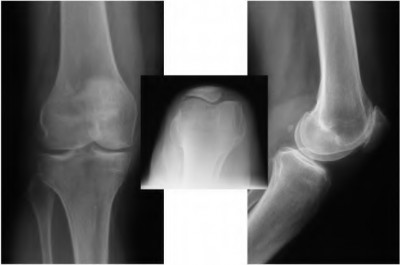

The radiograph seen in Figure A reveals varus alignment of the knee, with medial tibial deficiency; from this X-ray the patient appears to have unicompartmental arthritis. Treatment options for unicompartmental arthritis include high tibial osteotomy, interpositional arthroplasty, unicondylar knee replacement and total knee replacement. Interpositional arthroplasty became popular in the 1950’s when early outcomes analysis seemed to indicate good results; long term follow up in one study found 0/12 excellent results, with all patients requiring conversion to TKA. This procedure is no longer recommended due to the poor long term outcomes.

While an osteotomy is still used for young and active patients, unicompartmental or total knee arthroplasty have largely replaced this treatment in older patients. Advantages of UKA and TKA include more predictable relief of pain, quicker recovery, and better long-term results. Criteria for UKA include limited unicompartmental disease, no more than a fixed 10 degrees of varus or 5 degrees of valgus deformity from neutral and an intact anterior cruciate ligament with no signs of medial lateral subluxation of the femur on the tibia; this patient is therefore not a good candidate for this procedure.

Total knee arthroplasty can be used to provide predictable pain relief in a patient with unicompartmental and tricompartmental degenerative disease and varus malformation of the knee and for this patient is the best option.

Figures A and B depict radiographs of a unicompartmental knee arthroplasty (UKA). UKA kinematics have been shown to most closely approximate native knee kinematics.

In an in vitro cadaver study, Patil et al found that TKA significantly changed knee kinematics while the unicompartmental replacement preserved normal knee kinematics.

Fisher et al performed a retrospective study comparing the short-term outcomes of small-incision unicompartmental knee arthroplasty (UKA) with standard total knee arthroplasty (TKA) in 91 consecutive patients older than 70 years. They found: 1) Blood loss was significantly more for the TKA group, as was the need for blood transfusion. 2) Patients with unicompartmental replacements had a much quicker return of function and discontinuation of pain medication. 3) While knee scores and ROM were similar preoperatively, both were better in the unicompartmental group at each postoperative time interval. 4) Narcotic use and length of hospital stay were also significantly less for the unicompartmental group. Therefore answers 2,3,4 and 5 are false.